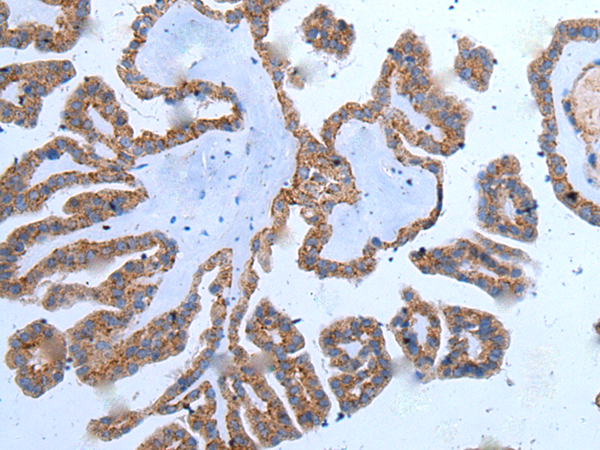

分类: 科研抗体货号: P12833别名:应用: WB,IHC反应种属: Human, Mouse